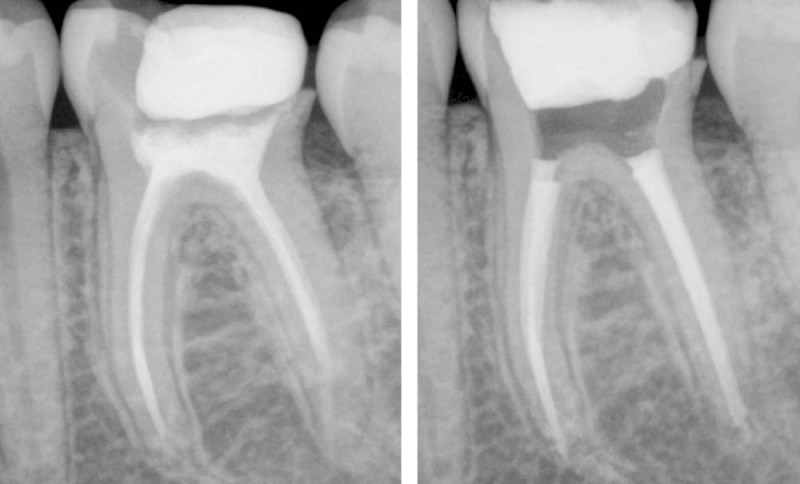

Environ 23 % des racines des patients ont déjà été traitées au niveau canalaire, parmi lesquelles 16 % seulement répondent aux critères de qualité d’un traitement endodontique [1]. Cela remis dans un contexte de dentisterie contemporaine ultra-préservatrice, le retraitement canalaire est la thérapeutique endodontique la plus usitée (fig. 1). Il ne s’agit pas seulement de nettoyer des canaux, mais bien de sauver des dents : en traitant des racines infectées, en guérissant des lésions osseuses inflammatoires d’origine endodontique, en assurant les fondations d’un projet prothétique destiné à assurer un rôle fonctionnel, esthétique.

La cavité d’accès (fig. 3) : aussi petite que possible, aussi large que nécessaire. Il s’agira de réaliser un nouvel accès aux canaux, sans compromettre ni le pronostic biomécanique (préservation des structures dentaires), ni le pronostic endodontique (lecture complète de l’anatomie). Avec quel matériel travailler correctement l’anatomie du plancher pulpaire tout en ayant une excellente visibilité : ultrasons ? fraises ?

La désobturation. Comment réaliser une désobturation efficiente ? Qui enlève un maximum de gutta sans compromettre l’intégrité dentinaire (butée, fausse route…) ? Désobturation mécanisée ? Manuelle ? Avec ou sans solvant ?

La perméabilité. Si elle a longtemps fait débat dans la littérature [4], elle permet aujourd’hui de sécuriser la trajectoire canalaire, de s’assurer de la vacuité du canal, et d’obtenir la longueur de travail. Comment s’assurer de la bonne reproductibilité de sa longueur de travail ? Vérification avec le localisateur d’apex ? Vérification radiographique ? Les deux ?

L’instrumentation (fig. 4). À l’instar de la cavité d’accès, le travail instrumental se doit d’être aussi petit que possible, aussi large que nécessaire, même dans un contexte de réintervention. Les canaux ayant déjà été préparés, il faudra s’adapter à la situation clinique : si les canaux étaient sous-préparés, un élargissement canalaire sera indispensable afin d’obtenir un volume suffisant pour désinfecter correctement. Si les canaux étaient surpréparés, un élargissement canalaire ne sera peut-être pas nécessaire. La réintervention nécessite-t-elle une certaine conicité instrumentale ? Une certaine largeur de travail (diamètre apical) ? Ai-je bien éliminé les anciens biomatériaux d’obturation ?